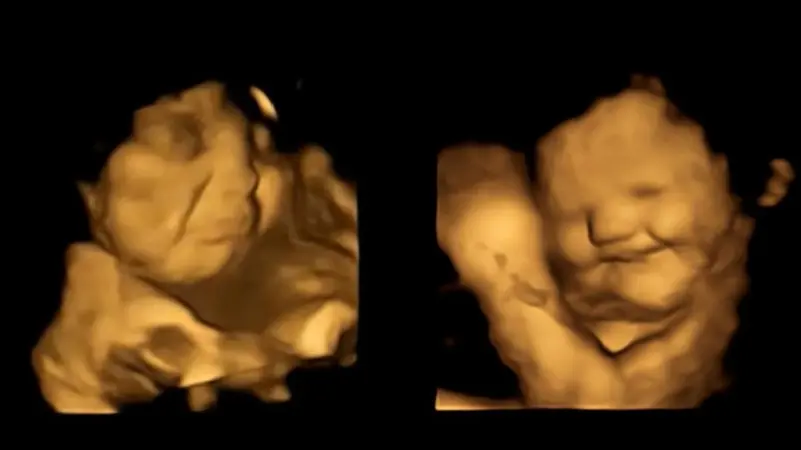

تلفزيون الفجر | تمكن علماء رصدوا وجوه الأجنة بموجات فوق صوتية، من التعرف إلى الحالة النفسية للأجنة وهم في أرحام أمهاتهم يتناولون الطعام لأول مرة، ووجدوا أن الجنين يبتسم حين يتذوق الجزر ويعبس تكشيرا عندما يكون اللفت هو الطعام، بحسب ما اتضح من تجارب خضعت لها 100 امرأة حامل، وابتلعت كل منهن كبسولة تحتوي على 400 ملليغرام من مسحوق الجزر أو الكرنب الملفوفي.

وبحسب ما بينت النتائج، فإن من تذوقوا نكهة الجزر اللطيفة أظهروا باستمرار استجابات أكثر “لوجه ضحوك” بعكس من تذوقوا الكرنب الملفوفي المر، حيث ظهر كل منهم بوجه عابس، لذلك ورد بالدراسة أن الكراهية الغريزية للطعم المر “هي منطقية من وجهة نظر تطورية، وهذا ما ساعد أسلافنا على تجنب السموم” لأن طعم معظمها منفر كرائحتها.

بالجزر يبتهج الجنين وبالكرنب الملفوفي ينزعج